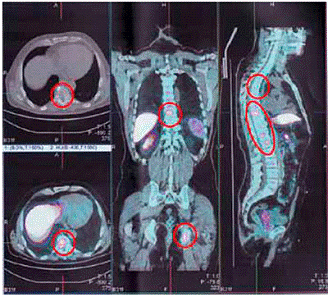

Эта стадия является последней. Рак уходит далеко за пределы единственной кости. Его метастазы разрастаются на внутренние органы, чаще всего задевает легкие, потом рак проникает в лимфатическую систему. Очень хорошо видны образования, при раке костей 4 стадии на фотографиях. Выживаемость при последней стадии рак крайне низкая (рисунок 2)

рисунок 2